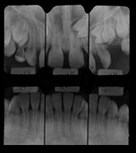

X-Rays and Cephalometric Tracings

pan xray ceph tracing measurements patienthist

Panoramic Intraoral Lateral Ceph Ceph Tracing Cephalometric Summary Patient History